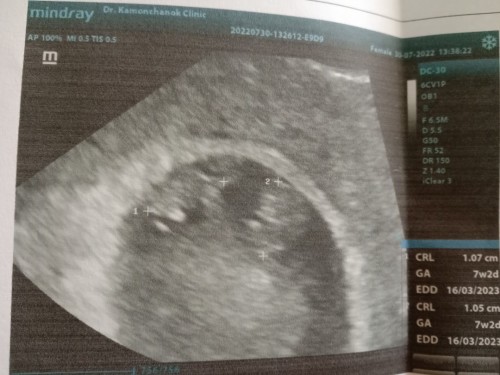

ตั้งครรภ์แฝด

ตอนนี้ตั้งครรภ์แฝดค่ะ อายุครรภ์8w2d แม่มีอาการแพ้ท้องหนักมาก รู้สึกเพลียเหนื่อยง่าย ทุกวันนี้นั่งๆนอนๆค่ะ ทำอะไรไม่ไหวเลยค่ะ จะมีผลเสียอะไรมั้ยคะ บางคนว่าเอาแต่นอน ลูกจะเอาอะไรมาแข็งแรง เกี่ยวกันมั้ยคะ เราก็พยายามเดิน ทำงานบ้าน แต่บางทีก็รู้สึกไม่ไหวจริงๆก็นอนพักค่ะ #ขอบคุณล่วงหน้านะคะ